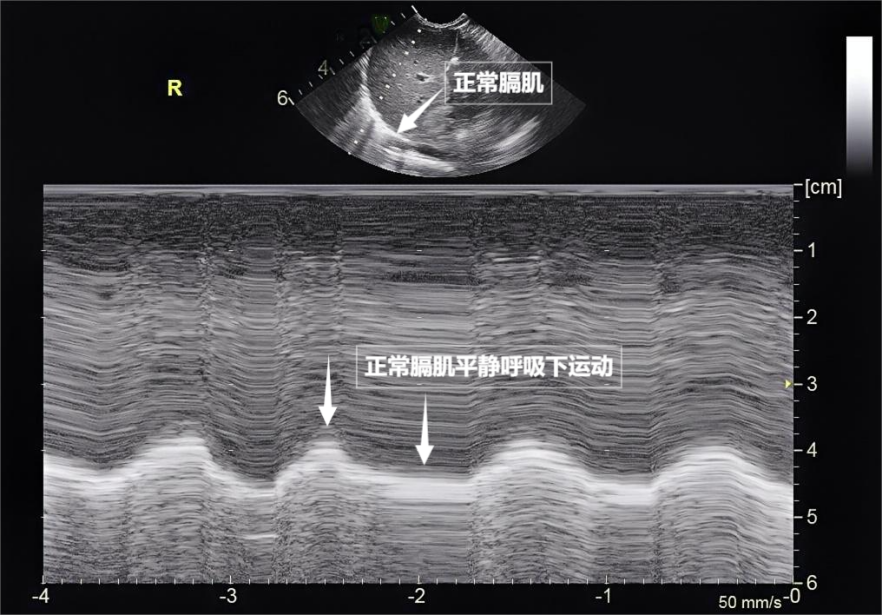

第三景:“呼吸的动力泵”的协同作战——呼吸肌肉

呼吸看似简单,实则是多组肌肉精密配合的“团体操”。肺部超声不仅能观察肺的形态,更能通过实时动态影像,“捕捉”这些呼吸肌的活动状态,为评估呼吸功能提供独特视角。膈肌是呼吸肌的“总指挥”,位于胸腔与腹腔之间。平静呼吸时,膈肌收缩下沉,胸腔容积扩大,空气自然吸入;舒张时,膈肌回升,肺部弹性回缩完成呼气。超声下可见膈肌呈光滑弧形,随呼吸规律上下移动(见下图)。肋间外肌则是“肋间隙的升降机”,收缩时上提肋骨,扩大胸腔前后径,辅助吸气。这对“黄金搭档”承担了日常呼吸70%以上的工作量,是维持呼吸的“主力军”。

图为正常膈肌超声表现

肺部超声这位“侦察兵”爱一配,通过观察肌肉激活顺序、测量膈肌厚度与移动度、捕捉肌肉矛盾运动,动态评估呼吸肌肉的变化,早期发现呼吸系统“超负荷运转”的信号,为医生调整治疗方案提供精准依据。